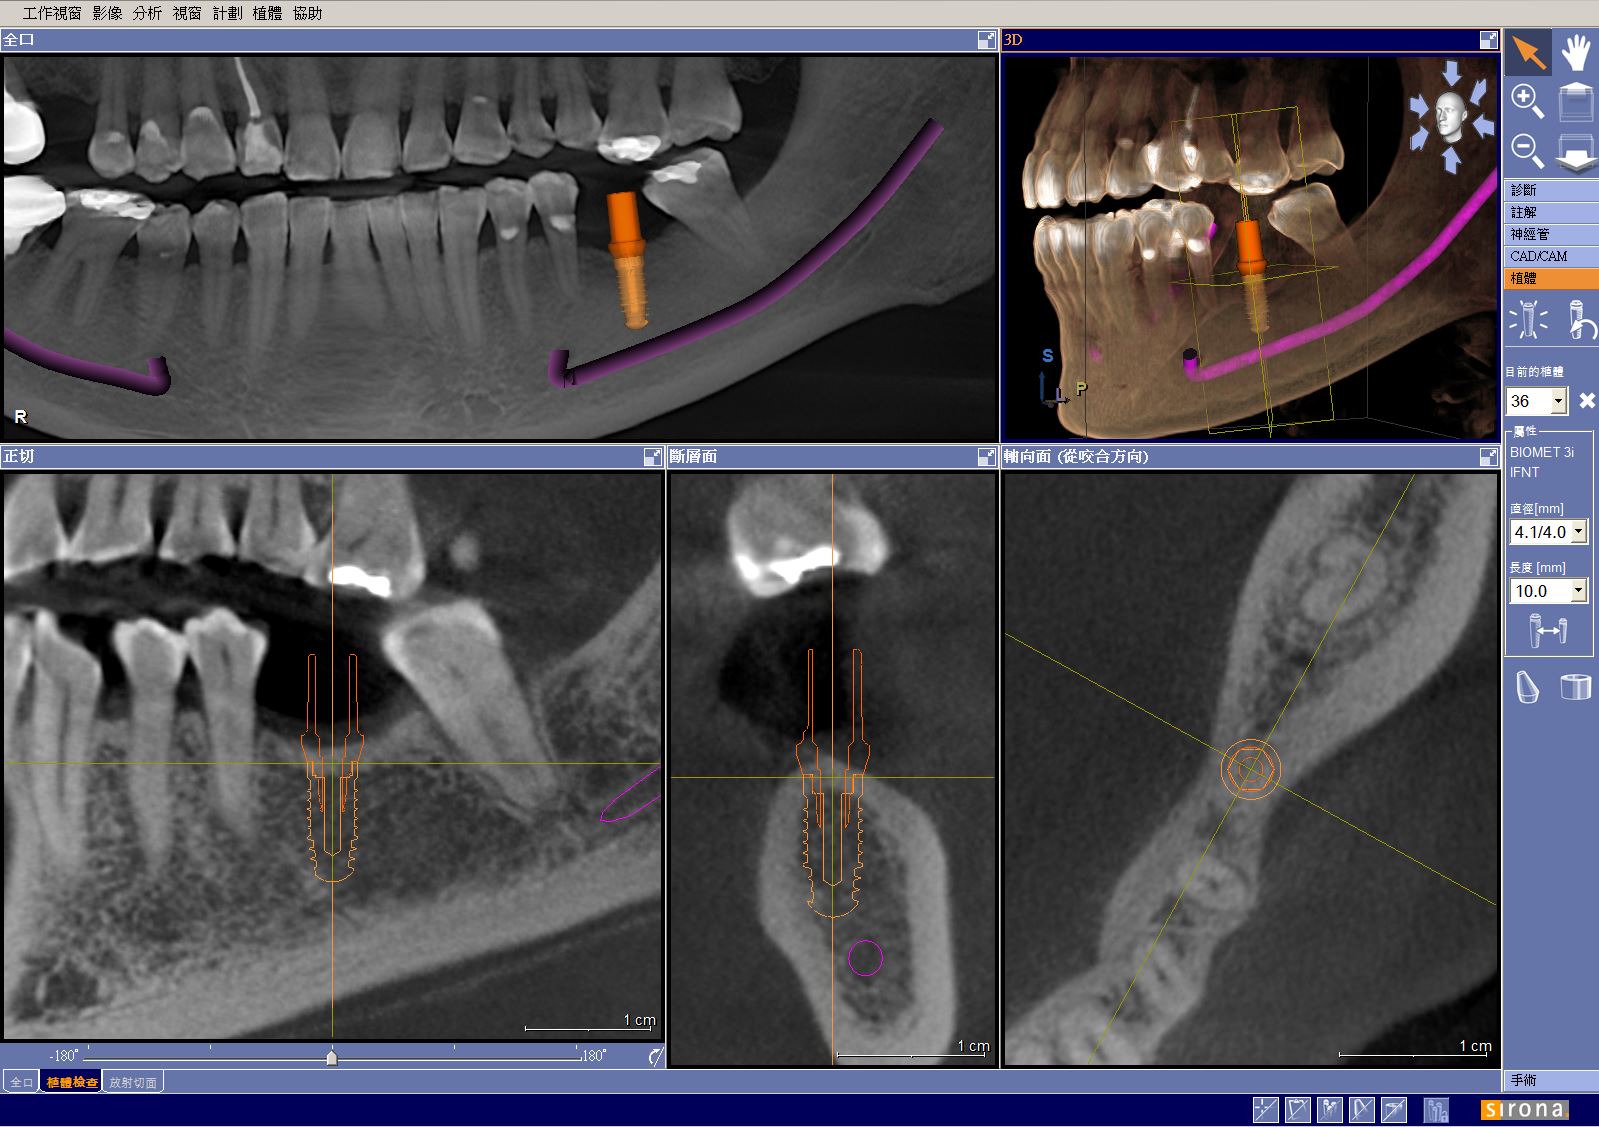

我們採用德國ORTHOPHOS XG 3D 電腦斷層掃描,以8x8x8 cm尺寸高解析模式拍攝,GALILEOS VIEWER 軟體介面的影像可隨移隨看,並依不同牙位需求,調整X.Y.Z軸向之斷層角度,進行植體模擬,由於簡易操作,除提高診斷效率外,亦可結合CREEC口內掃描儀,製作手術導板,藉此讓患者有更大的治療接受度!

GALILEOS VIEWER 軟體應用: